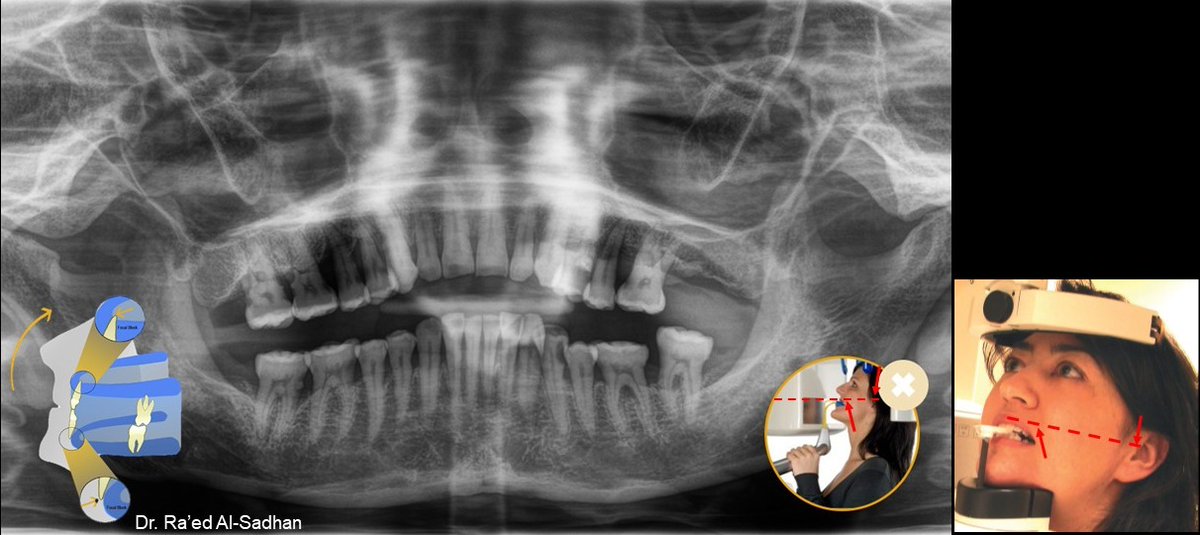

في المقابل لو نزل الذقن أكثر من اللازم أثناء التصوير البانورامي فلن يتوافق محور فرانكفورت للرأس مع الخط الضوئي في الجهاز وستخرج الأسنان من طبقة التصوير وتظهر صورتها مشوهة (وكأنه مبتسم).